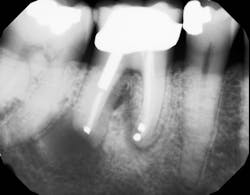

If definitive crown placement is delayed and the patient has excessive forces on the tooth or suffers from direct trauma, the tooth can fracture. In many cases, a decision must be made upon full bone healing versus the likelihood of crown fracture (figure 3–6). In addition, most studies show that full-coverage crowns are a main factor in determining long-term success of root canal therapy, with successes ranging from 92% for teeth receiving crowns compared to 35% for those not receiving crowns after a one- to five-year follow-up.2 In another study on molar teeth five years after root canal therapy, teeth that had crowns placed had a success rate of 78% versus 36% without crown coverage.3